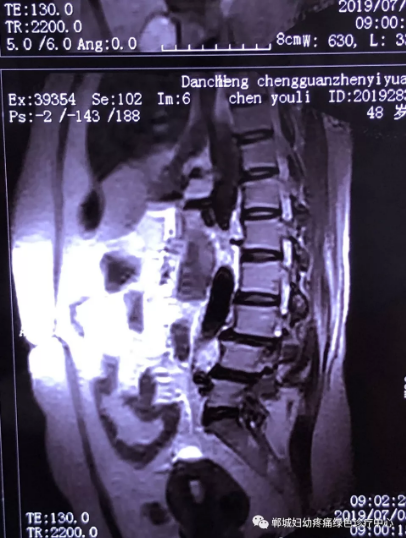

2年前,雙樓鄉(xiāng)的陳女士不小心摔了一跤后出現(xiàn)腰痛,當(dāng)時(shí)到藥店買了膏藥來貼,疼痛減輕了一些,但是從此以后反反復(fù)復(fù)出現(xiàn)腰痛。到處進(jìn)行治療,不見好轉(zhuǎn),最近腰痛加重了,痛得受不了,出現(xiàn)行走后甚至持續(xù)的雙下肢后側(cè)或后外側(cè)放射性的疼痛麻木、間歇性跛行等癥狀。陳女士趕忙去醫(yī)院治療,做了磁共振檢查后確診為腰椎滑脫、腰椎反弓。醫(yī)生都告訴她需要手術(shù)治療。隨后她又帶著片子咨詢了好幾家醫(yī)院,結(jié)果都是一樣,她已經(jīng)做好了手術(shù)的打算。

治療前

不經(jīng)意間聽到有人說醫(yī)院疼痛科可以不吃藥不打針,用無痛苦、無創(chuàng)傷的方法治療腰痛。陳女士就抱著試試看的心理來到了鄲城縣婦幼保健院疼痛科,疼痛科時(shí)慶祥主任詳細(xì)了解病情,結(jié)合腰椎磁共振及體征后告訴陳女士她不用手術(shù),通過腰椎脊柱定位周期減壓牽引系統(tǒng)(外星艙)也能解決腰痛、腰椎滑脫、腰椎反弓這些問題。陳女士未曾想到經(jīng)過十五天的治療后腰部及下肢放射性疼痛癥狀基本消失。陳女士感到十分激動(dòng)與感謝,就在當(dāng)?shù)匦l(wèi)生院做了一個(gè)腰椎正側(cè)位x片和之前的片子作對(duì)比,發(fā)現(xiàn)腰椎滑脫明顯改善。她說道:感謝鄲城縣婦幼保健院疼痛科的所有醫(yī)護(hù)人員、感謝外星艙脊柱減壓治好了我的腰痛,也感謝告訴我來這里的人,她的一句話,讓我省了好幾萬元的手術(shù)費(fèi)!